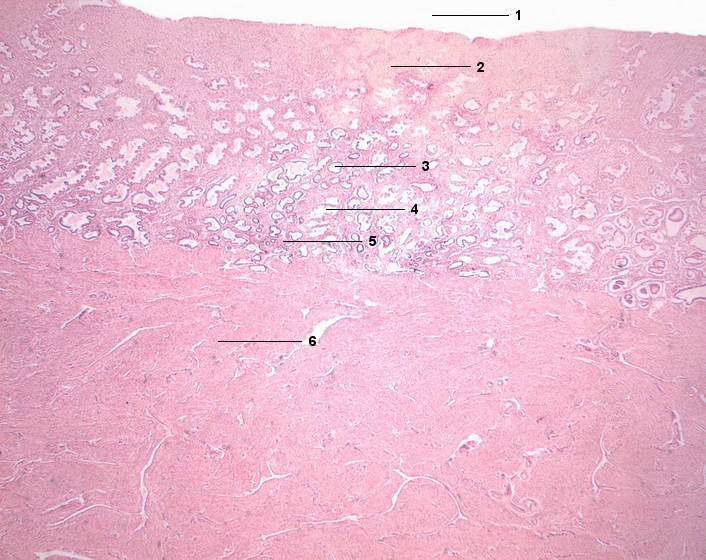

1 Cavum uteri, Uteruslichtung

2 Endometrium, Str. functionale (Zona compacta)

3 Stratum functionale, Zona spongiosa

4 Glandula uterina

5 Stratum basale

6 Myometrium